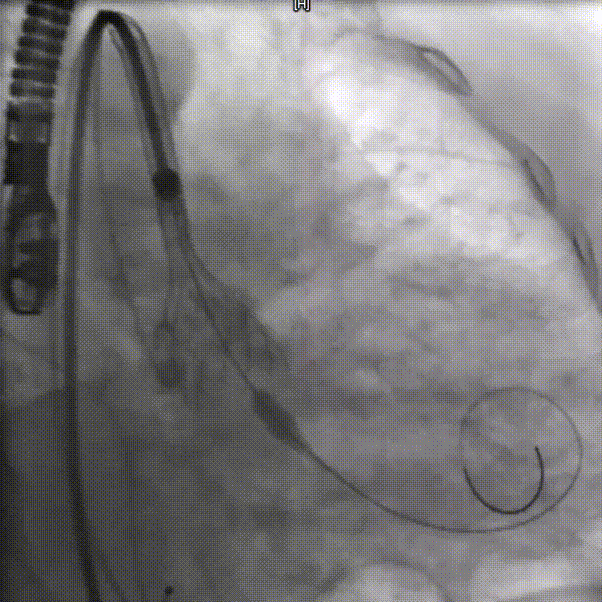

瓣下3mm定位

释放到工作位,瓣下5mm左右

缓慢脱钩

左冠窦侧微量反流

22mm球囊后扩

患者压差从163mmHg降为6mmHg,效果显著。